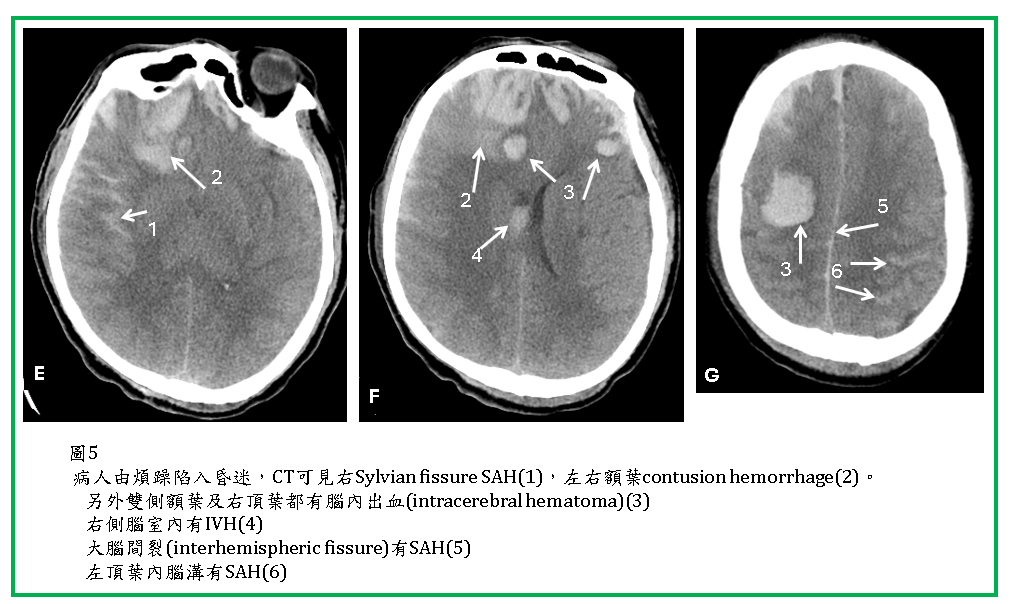

外傷性SAH (Traumatic SAH)

外傷性蜘蛛網膜下腔出血(traumatic subarachnoid hemorrhage, SAH) 很常見,可以單獨發生,但更常合併brain contusion, SDH, EDH。

Traumatic SAH 於CT上常見於大腦腦溝(sulcus),腦裂(Sylvian fissure, interhemispheric fissure),腦池(如suprasellar cistern),以及小腦天幕旁 (tentorial edge)。CT對於SAH及IVH的診斷很敏銳,但在成年人interhemispheric fissures內的falx鈣化與SAH容易混淆。位於tentorium edge 以及interhemispheric fissures內的SAH,與SDH不易區分,coronal reconstruction 有助於鑑別。